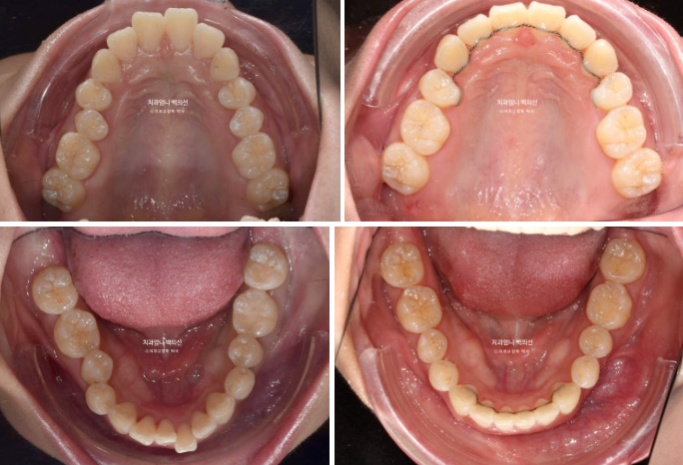

23년 3월부터 24년 5월까지 1년 2개월간 52개의 장치를 낀 후 재제작 당시의 모습 보여드리겠습니다.

과개교합은 잘 개선이 되었습니다.

발치공간이 아직 남아있고 앞니 각도의 개선이 더 필요합니다.

아래 어금니들은 사랑니 공간으로 잘 이동했습니다.

한달간 추가장치 제작기간을 기다려 24년 6월부터 두번째 세트의 장치를 끼기 시작했습니다.

25년 1월까지 7개월간 추가장치를 끼고 치료가 마무리 되었습니다.

23.02-25.01

전 후 비교입니다.

총 치료기간은 1년 11개월이고 실제 장치를 낀 기간은 1년 9개월입니다.